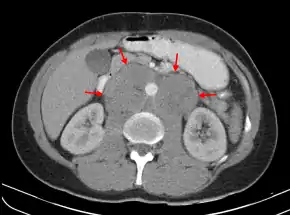

A CT scan of axillary lymphadenopathy in a 57-year-old man with multiple myeloma.

Retroperitoneal lymphadenopathies of testicular seminoma, embrace the aorta. Computed tomography image.